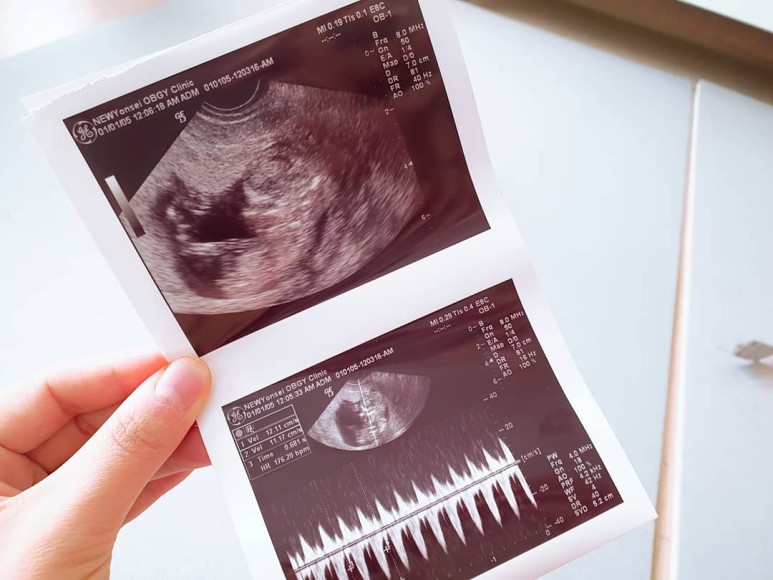

질 초음파하자마자 꼿꼿이 나타나는 아기 집과 아기.6주 6일이나 되니 심장도 두근거렸다.

비행기타고 괌 여행가고 강행군 물놀이에 피임약도 먹어서 많이 걱정했는데 담당선생님 말로는 아이가 지금 건강하니까 괜찮다고..

초음파로 본 달콩은 건강했고 열이 나는 다행히 나에 비해 심박수가 고열은 아니었다.